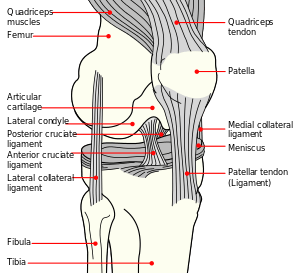

Anatomy of the knee

The patella is a triangular sesamoid bone which is embedded in tendon. It rests in the patellofemoral groove, an articular cartilage-lined hollow at the end of the thigh bone (femur) where the thigh bone meets the shin bone (tibia). Several ligaments and tendons hold the patella in place and allow it to move up and down the patellofemoral groove when the leg bends. The top of the patella attaches to the quadriceps muscle via the quadriceps tendon,[1] the middle to the vastus medialis obliquus and vastus lateralis muscles, and the bottom to the head of the tibia (tibial tuberosity) via the patellar tendon, which is a continuation of the quadriceps femoris tendon.[13] The medial patellofemoral ligament attaches horizontally in the inner knee to the adductor magnus tendon and is the structure most often damaged during a patellar dislocation. Finally, the lateral collateral ligament and the medial collateral ligament stabilize the patella on either side.[1] Any of these structures can sustain damage during a patellar dislocation.